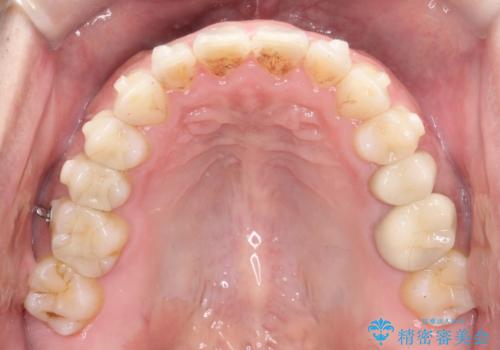

【インビザライン】前歯の隙間を閉じたい

- 前歯の隙間を主訴に来院されました。

マウスピース矯正にて、隙間を綺麗に閉じることができ満足していただきました。

前歯の隙間を閉じる際は、前歯部の突き上げが懸念されるため、適切な治療計画が必要となります。